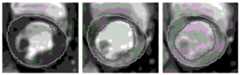

图4a为本发明实施例中心脏灌注磁共振图像的配准前的图像;4a is an image before registration of a cardiac perfusion magnetic resonance image in an embodiment of the present invention;

图4b为本发明实施例中心脏灌注磁共振图像的配准后的图像。FIG. 4b is an image after registration of a cardiac perfusion magnetic resonance image according to an embodiment of the present invention.